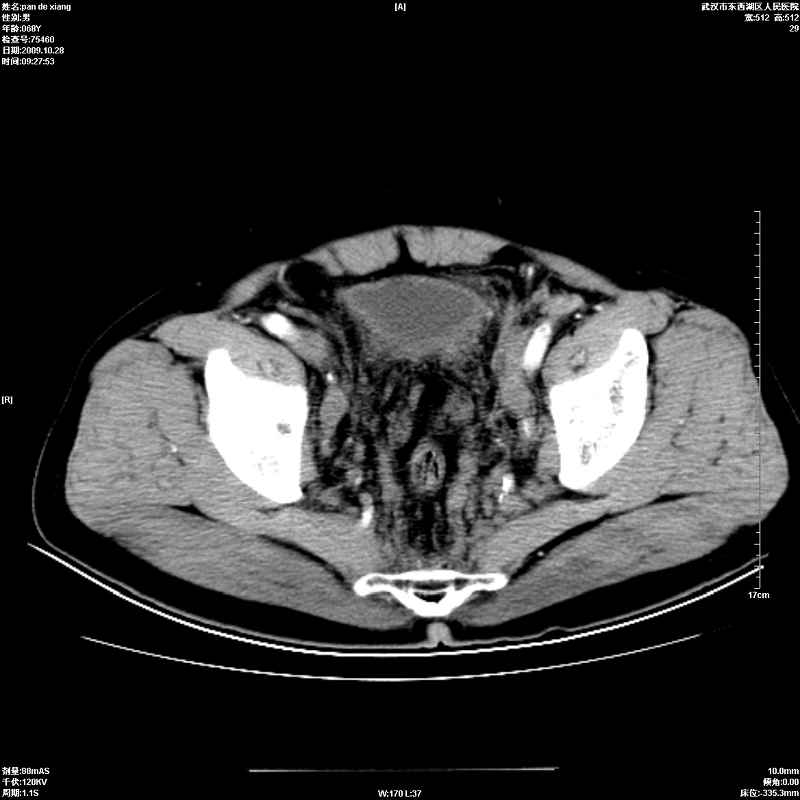

以下是引用杀毒软件在2009-10-28 20:41:00的发言:[br]结合临床考虑---白血病双肾改变或淋巴瘤。

以下是引用zxl51642在2009-10-29 9:59:00的发言:[br]结合临床“单克隆免疫球蛋白血症”,考虑双肾为继发损害并肾功能不全(尿中大量igg及少量iga、igm等大分子免疫球蛋白滤出所致继发损害),椎前软组织肿块为髓外造血。与浆细胞瘤有区别,平扫时有战友说的很清楚。